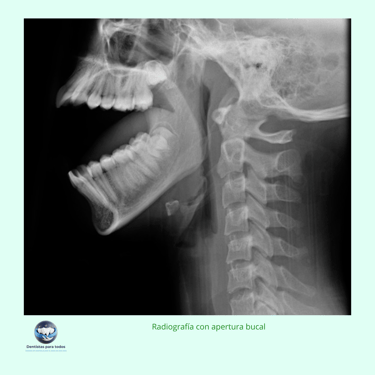

Toma de Radiografías: Se realizan radiografías específicas de la ATM, como la radiografía panorámica, la radiografía transcraneal o la radiografía transmaxilar, para obtener imágenes detalladas de las estructuras óseas.